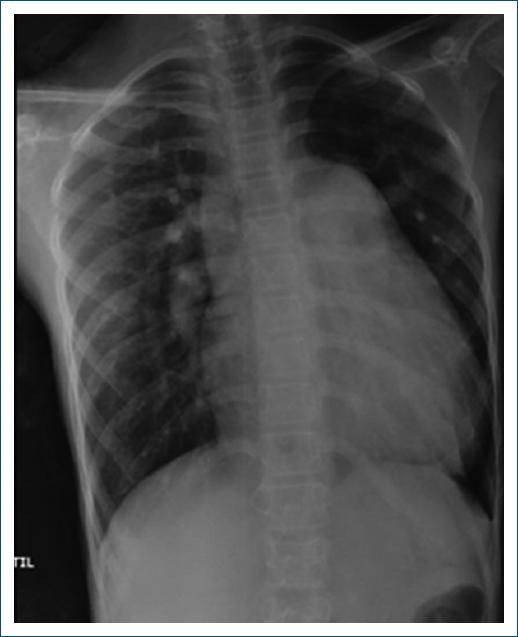

A 10-year-old girl with 2 months of recurrent epistaxis, fatigue, and severe cardiomegaly was referred for a cardiology consultation (Fig. 1).